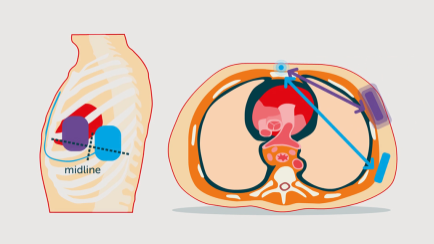

Fat Tissue DFT Thumbnail

The effect of fat tissue on the defibrillation threshold

Watch the animation about the effect of fat tissue on the defibrillation threshold.